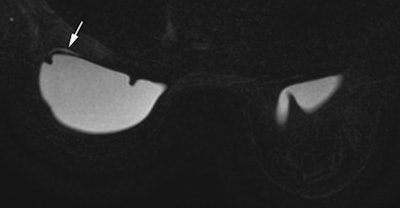

Rather than a clear rupture, a "perspiring" implant, where gel slowly leaks through the porous membrane, is the most common problem that surgeons report, according to Dr. Corinne Balleyguier, head of breast imaging in the department of radiology at the Institut Gustave Roussy (IGR)in Villejuif, France.

"Perspiration can't be confirmed or assessed by ultrasound, but it accounts for 60% of problems related to defective implants," she commented. "Ultrasound may depict a slight fluid slick around the implant, but this might be normal breast fluid or perspiring gel."

In research involving 270 implants removed at the IGR, MRI with dedicated silicone sequences was helpful in diagnosis of perspiration. In the 93 perspiring implants, 43 out of 49 ultrasound exams were normal, with six false positives for rupture. Sixteen MRI examinations were also performed on the 93 perspiring implants. Seven out of nine MRI exams showed perspiration because MRIs were acquired with silicone sequences; five out of seven MRI exams were normal, but these MRIs were acquired without silicone sequences.

Out of the 270 removed implants, there were 13 ruptures. Ultrasound was available for 12 of these, with six yielding normal imaging results and six abnormal. Only one MRI exam was available, and it was abnormal.

Because the gel is locally aggressive, extracapsular rupture yields early and clear clinical signs such as pain and swelling, which are easy to spot on ultrasound. Axillary lymph nodes must also be checked by ultrasound for siliconoma in case the implant is only slightly compromised, leading to slow leakage or a "perspiring" capsule, which does not give any clear clinical symptoms or radiological evidence in breast ultrasound, she explained.